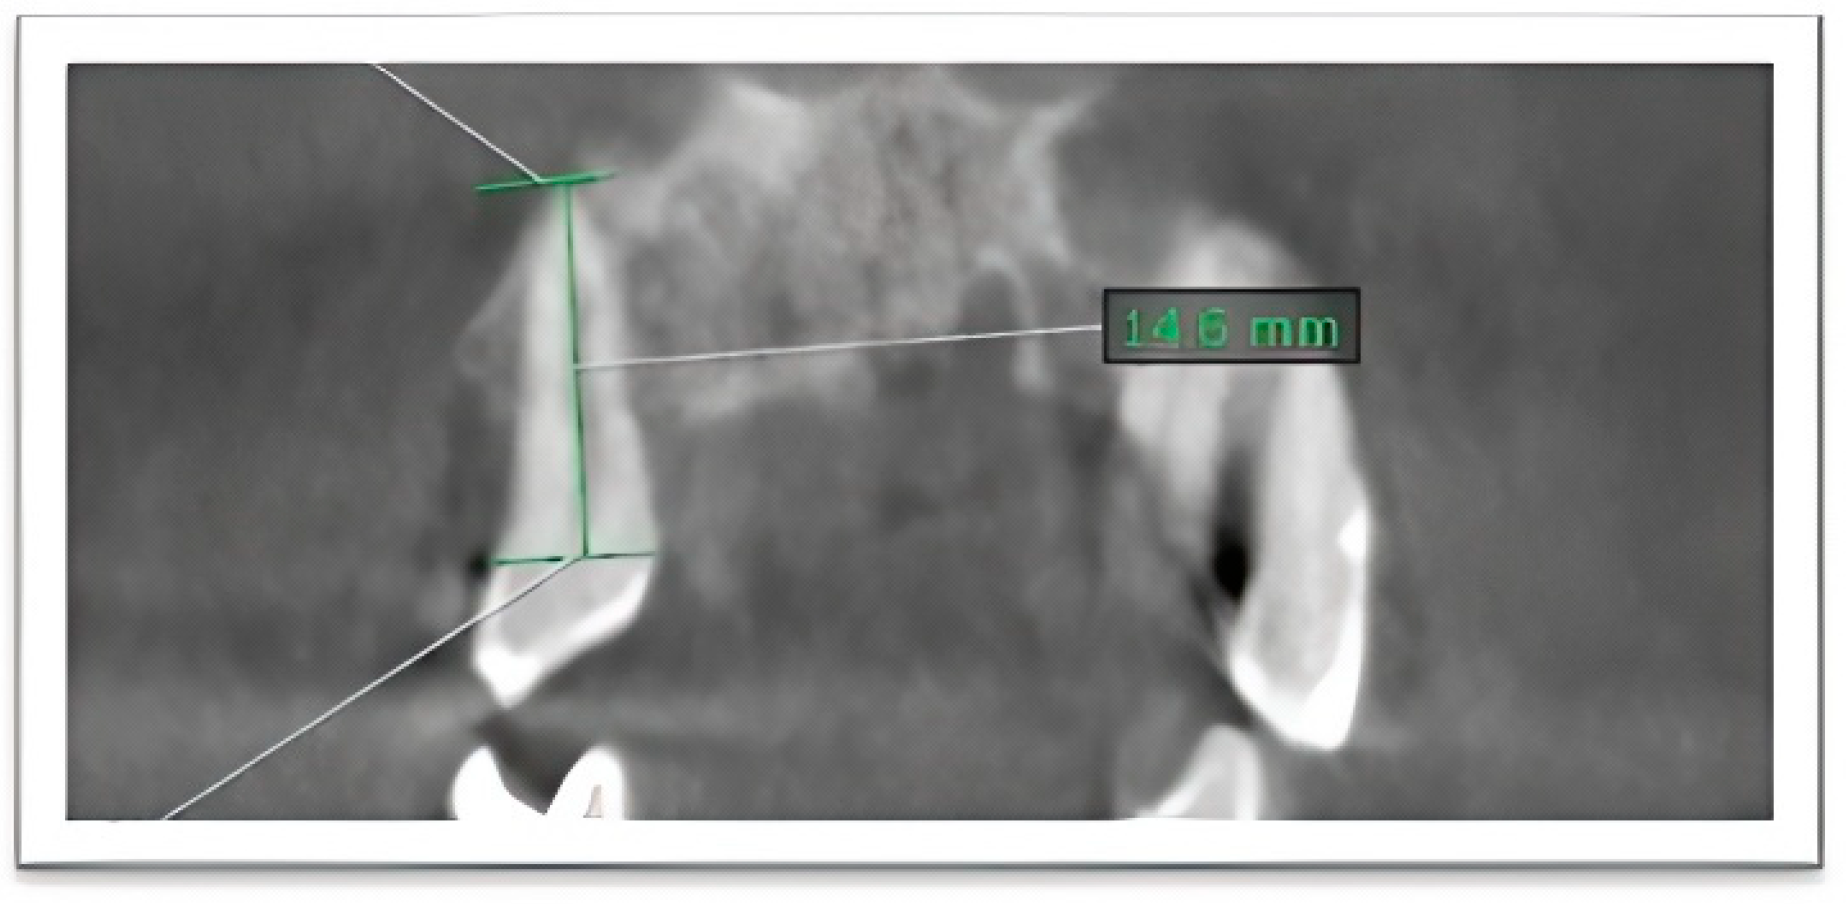

- (1)

- Root length (coronoapical length) was measured as the linear distance from the midpoint of the CEJ to the most apical point of the root along the long axis of the tooth (Figure 1).